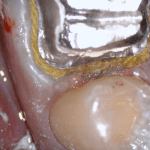

In this clinical video we demonstrate how to scan a molar preparation for the replacement of a crown with recurrent decay and open margins. The molar was root canal treated and the tissue was inflamed. the preparation was imaged and a temporary was fabricated to allow the tissue to heal properly.

The main point of this video is to show how to capture the contacts of the adjacent teeth and the deep marings